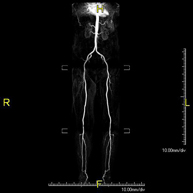

Prova diagnòstica no invasiva que consisteix en l'estudi vascular del sector aorto-ilíac i dels vasos arterials de les dues extremitats inferiors, am l'obtenció d'imatges d'alta definició anatòmica mitjançant l'ús d'un camp electromagnètic i ones de ràdio (amb un emissor i un receptor). És indispensable l'ús de contrast paramagnètic (Gadolini). No obstant, no utilitza radiació ionitzant. La qualitat de les imatges permet realitzar reconstruccions en 2D i 3D. Està especialment indicat en aquells pacients en els que hi ha sospita de malaltia vascular a les dues extremitats, en pacients amb malaltia vascular de les dues extremitats com a mapa vascular abans del tractament (percutani o quirúrgic), com a mapa vascular prequirúrgic en pacients amb lesions òssies o musculars que requereixin cirurgia, etc. - Angio-RM d'Artèries renals

Prova diagnòstica no invasiva que consisteix en l'estudi de l'artèria aorta abdominal per obtenir imatges d'alta definició anatòmica mitjançant l'ús d'un camp electromagnètic i ones de ràdio (amb un emissor i un receptor). És indispensable l'ús de contrast intravenós paramagnètic (Gadolini). No obstant, no utilitza radiació ionitzant. La qualitat de les imatges permet realitzar reconstruccions en 2D i 3D. Està especialment indicada en pacients amb sospita de malaltia vascular de les dues extremitats, en pacients amb malaltia vascular de les dues extremitats com a mapa vascular abans del tractament (percutani o quirúrgic), com a mapa vascular prequirúrgic en pacients amb lesions òssies o musculars que requereixin cirurgia, etc. - Angio-RM Lesió de parts toves